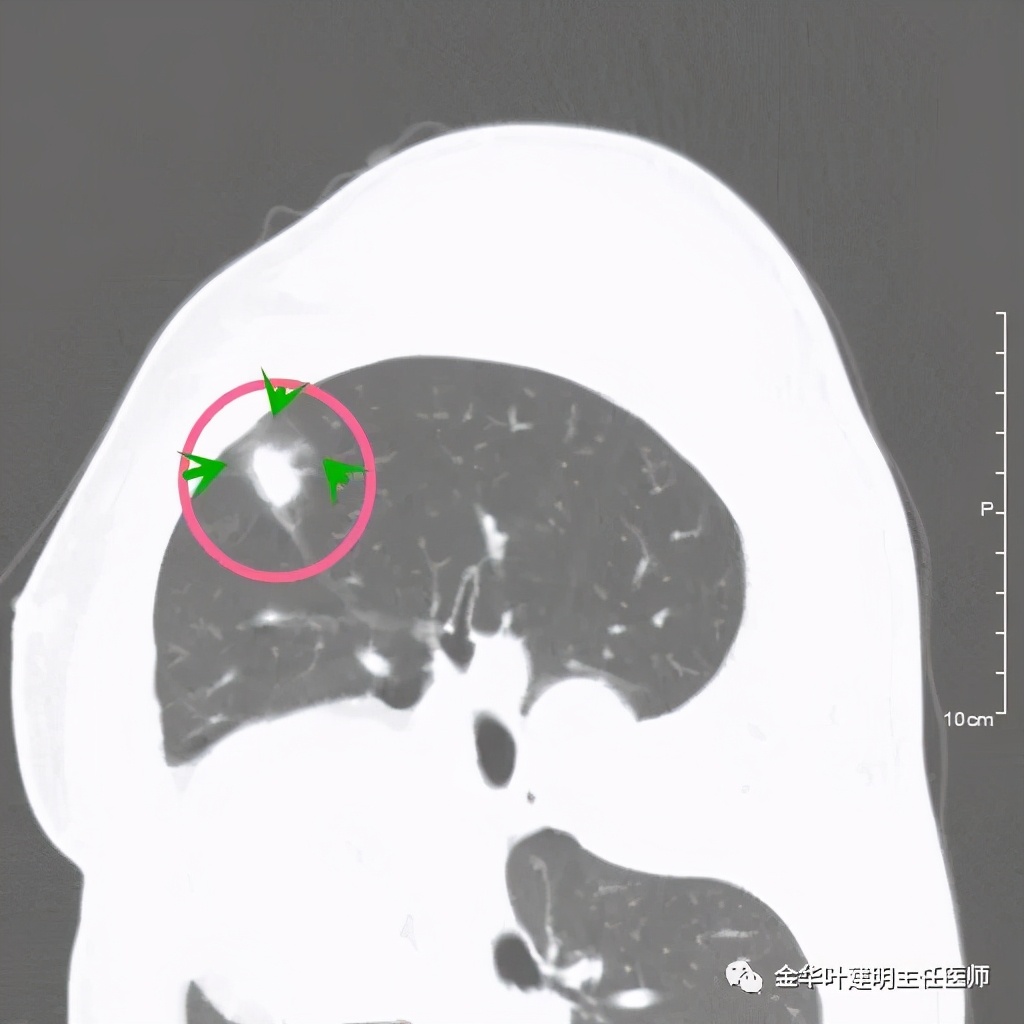

病灶实性,但收缩力弱,绿色箭头示病灶边缘有一圈晕征(模糊且均匀)

病灶实性,但收缩力弱,没有细毛刺征,实性部分比较圆润,绿色箭头示病灶边缘有一圈晕征(模糊且均匀)

此层面红色箭头示有卫星灶,粉色箭头示主病灶

红色示卫星灶,粉色示病灶,绿色示边缘晕征

此层面相对最不舒服,病灶表面不平整。桔色箭头示血管进入病灶,但仍有绿色箭头示病灶有晕征(边缘是模糊的,不似肿瘤那种细毛刺且相对清楚轮廓)